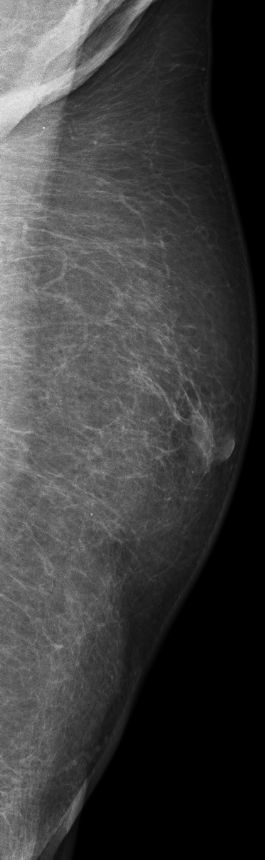

| DCIS | 80-jähriger Mann mit einem Knoten rechts retromamillär. Mammographie: Dichter Knoten mit multiplen Mikroverkalkungen unmittelbar periareolär. Histologie: papilläres DCIS, G2, 19 mm, ER: 12/12, PR: 6/12, Ki-67: 20%. Th.: Exzision, Radiatio der Mamma, TAM über 5 Jahre | ||||

links MLO![]() | |